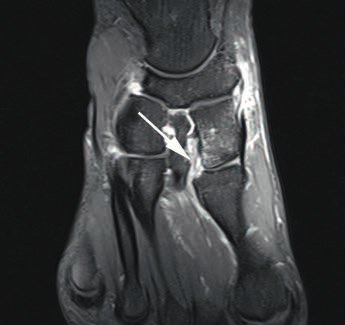

Die dorsalen und plantaren Anteile des Lisfranc-Bandkomplexes lassen sich kernspintomografisch gut und präzise darstellen (Abb. 6) 28. Wichtig für die Praxis erscheint in diesem Zusammenhang die enge Zusammenarbeit zwischen Radiologen und Orthopäden, denn nur eine akkurate und symptomorientierte Durchführung des Schnittbildverfahrens ermöglicht die entsprechende Darstellung der Bandverletzung mit der gewünschten diagnostischen Sicherheit 29. Bei einer Standardabbildung des Vorfußes im MRT werden die Lisfranc-Bänder oft nicht exakt dargestellt, was eine Aussage zum Ausmaß der Verletzung problematisch macht. Zur exakten Darstellung von knöchernen Verletzungen bietet das Computertomogramm die beste Aufiösung 30.

Auf dorsoplantaren Röntgenaufnahmen unter Belastung kann im Vergleich beider Seiten das Auseinanderweichen der Basen von Metatarsale I und II dargestellt werden. Bei kompletten Bandzerreißungen findet sich auf den Seitaufnahmen unter Belastung eine Abflachung des Längsgewölbes. Mit MRT-Aufnahmen lassen sich das Ausmaß der Bandverletzung sowie mögliche Mikrofrakturen oder die diskrete Dislokation der Lisfranc-Gelenklinie darstellen. Eine noch bessere Knochenauflösung bietet das CT. Ein konservatives Vorgehen hat sich bei Grad-I-Verletzungen bewährt, während bei Grad-II- und ‑III-Läsionen die Reposition mit Stellschraube die Behandlung der Wahl beim Sportler darstellt. Verschiedene Studien unterstreichen die Bedeutung einer frühen Diagnose und Therapie für ein gutes Behandlungsergebnis. Eine verzögerte Diagnose steigert das Risiko degenerativer Veränderungen im Tarsometatarsalgelenk. Liegen erst einmal irreversible Knorpelschäden vor, stellt häufig die Arthrodese des Tarsometatarsalgelenks die einzige verbleibende Therapieoption dar. Eine verzögerte Diagnose und ein verzögerter Behandlungsbeginn erhöhen das Risiko für eine dauerhafte Einschränkung der Sportfähigkeit.